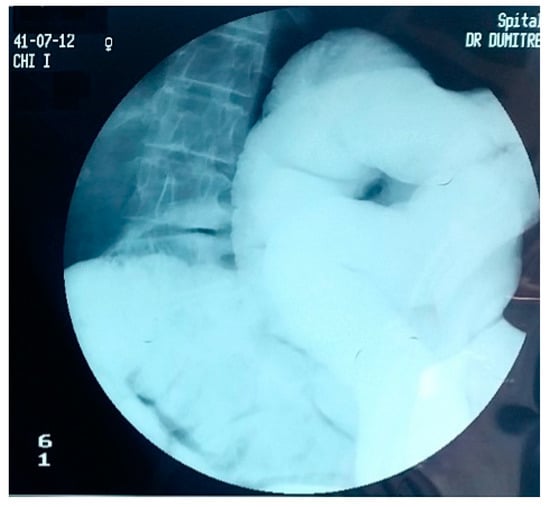

4. Diagnostic Criteria for the Acquired Megacolon